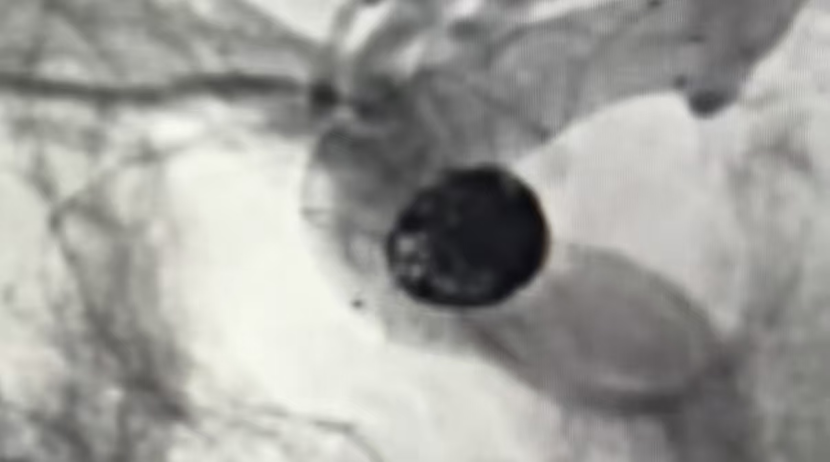

手术过程顺利,术后造影证实动脉瘤栓塞致密,载瘤动脉通畅无阻。